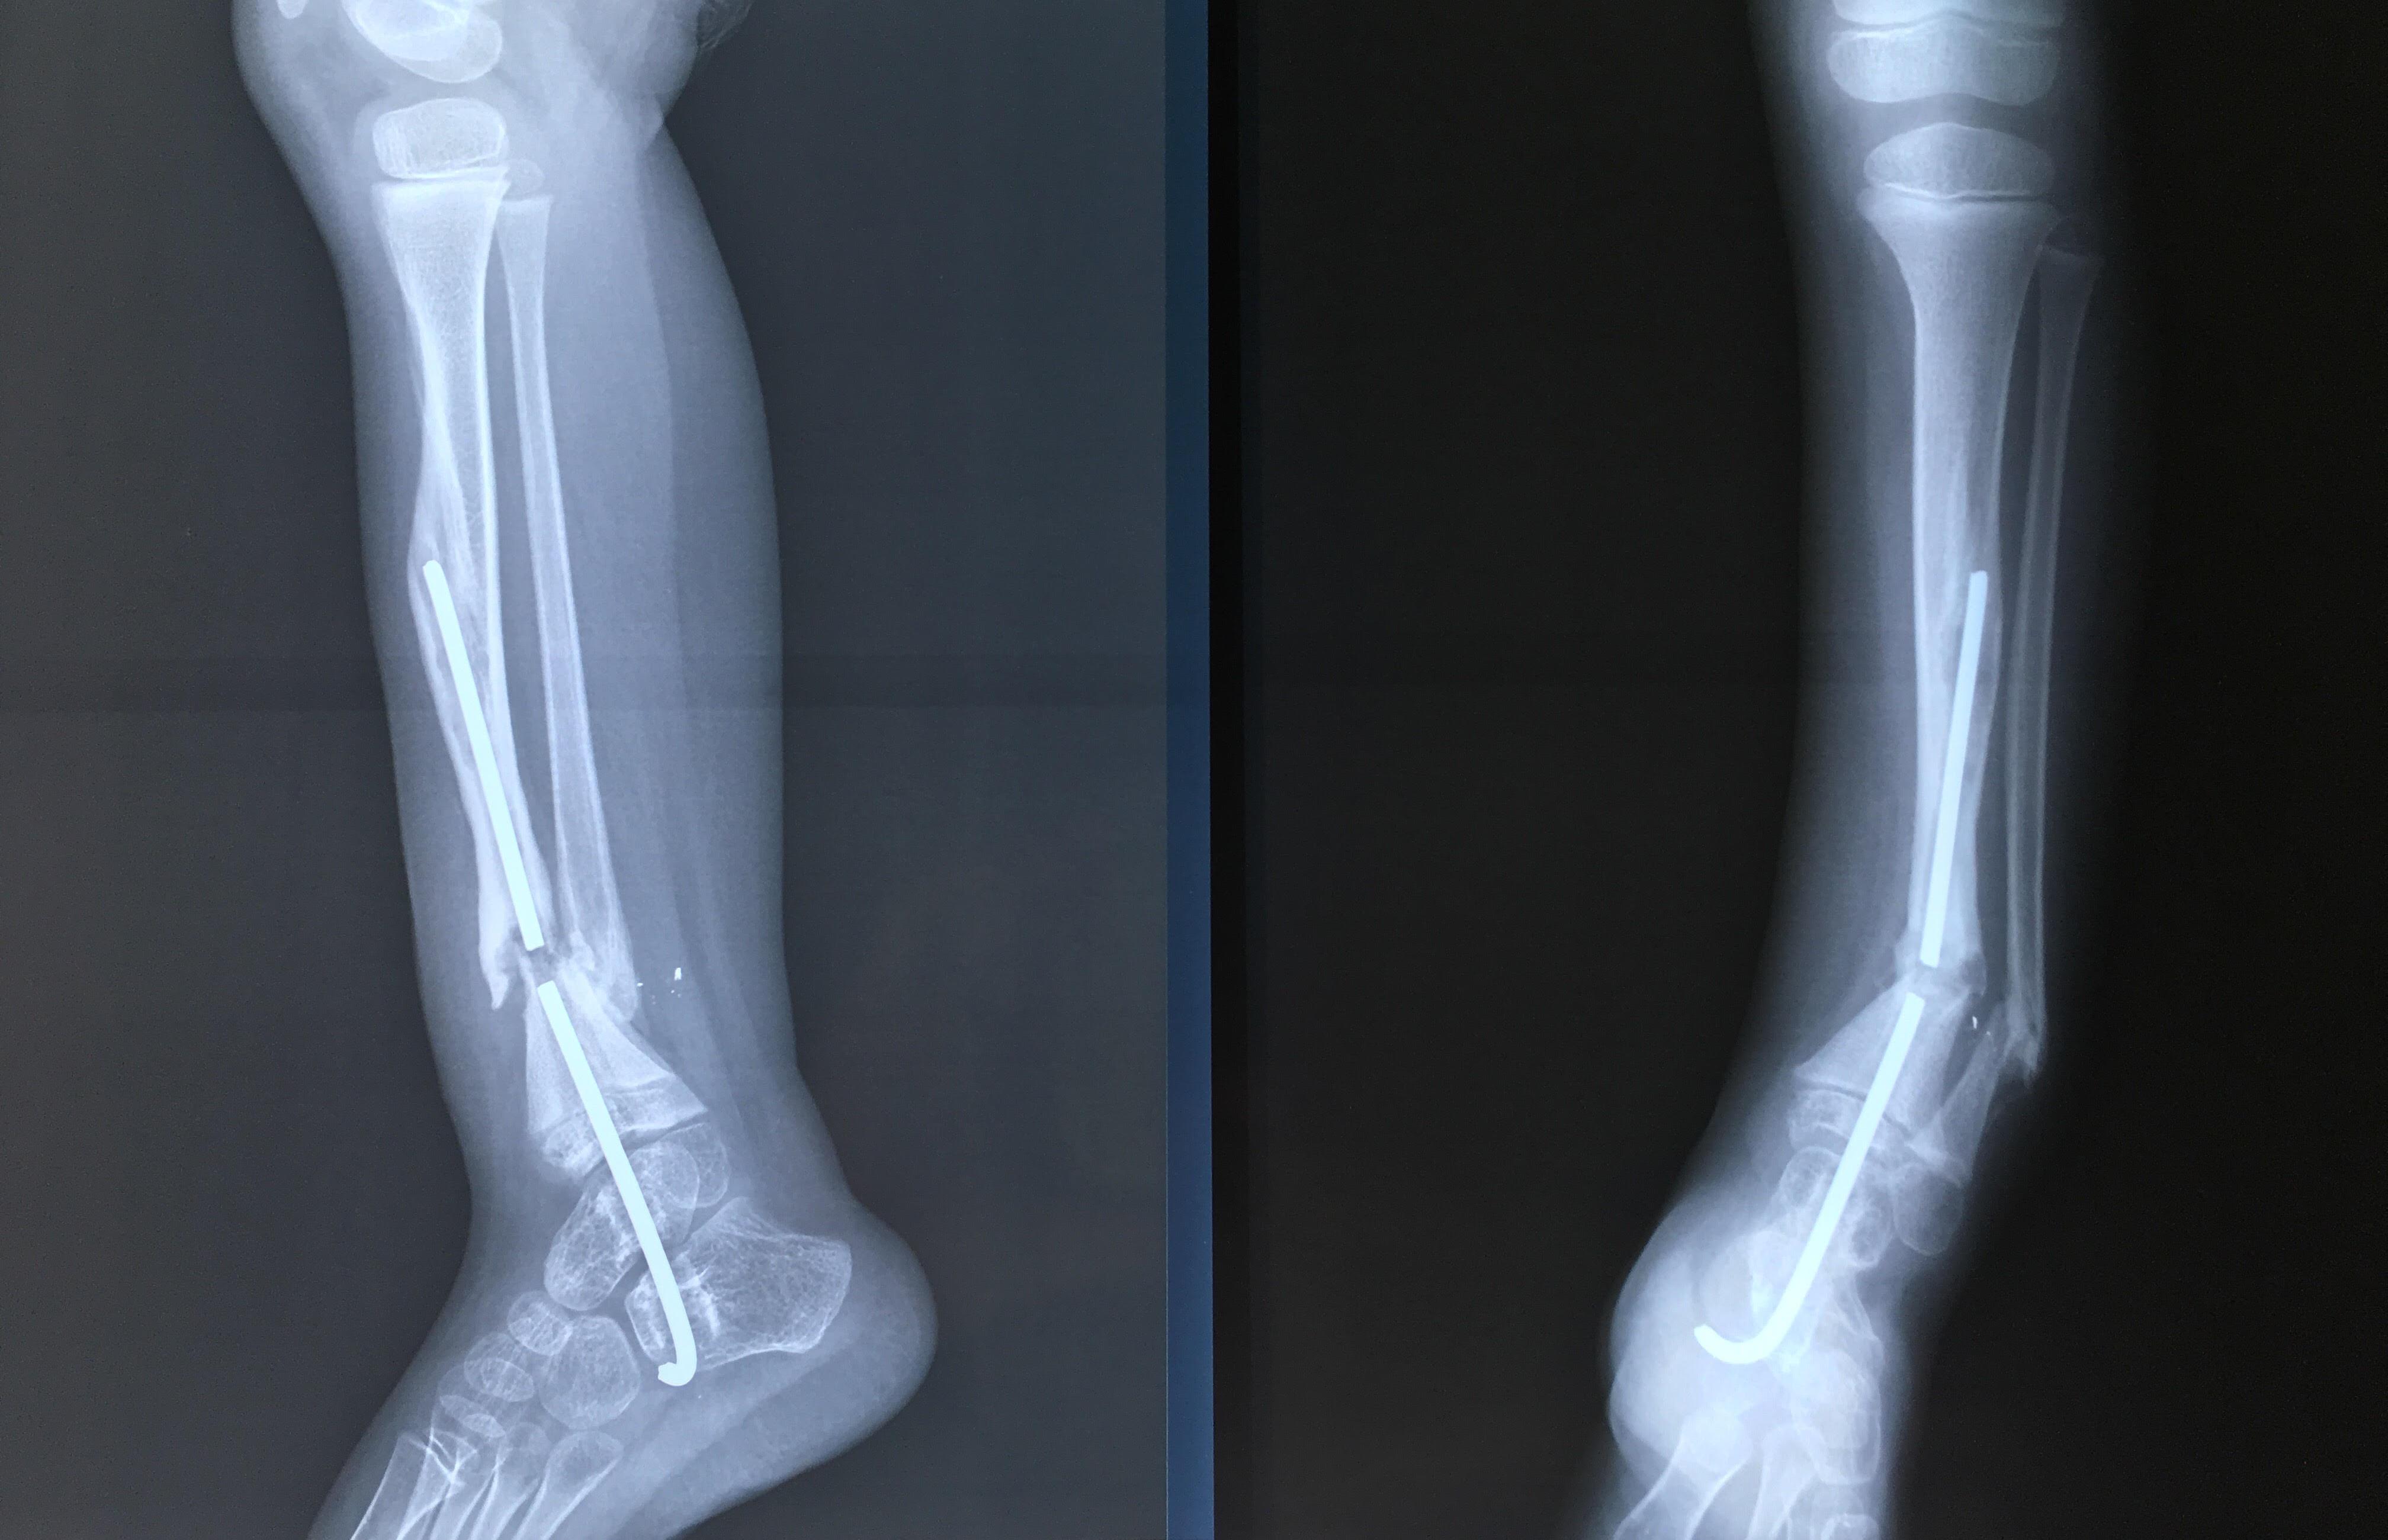

Phẫu thuật thành công ca bệnh hiếm gặp...khớp giả bẩm sinh xương chày

26/06/2019 17:00

Đã xem: 2881

Bệnh viện Chấn thương- Chỉnh hình Nghệ An, vừa phẫu thuật thành công cho bệnh nhi khớp giả bẩm sinh xương chày